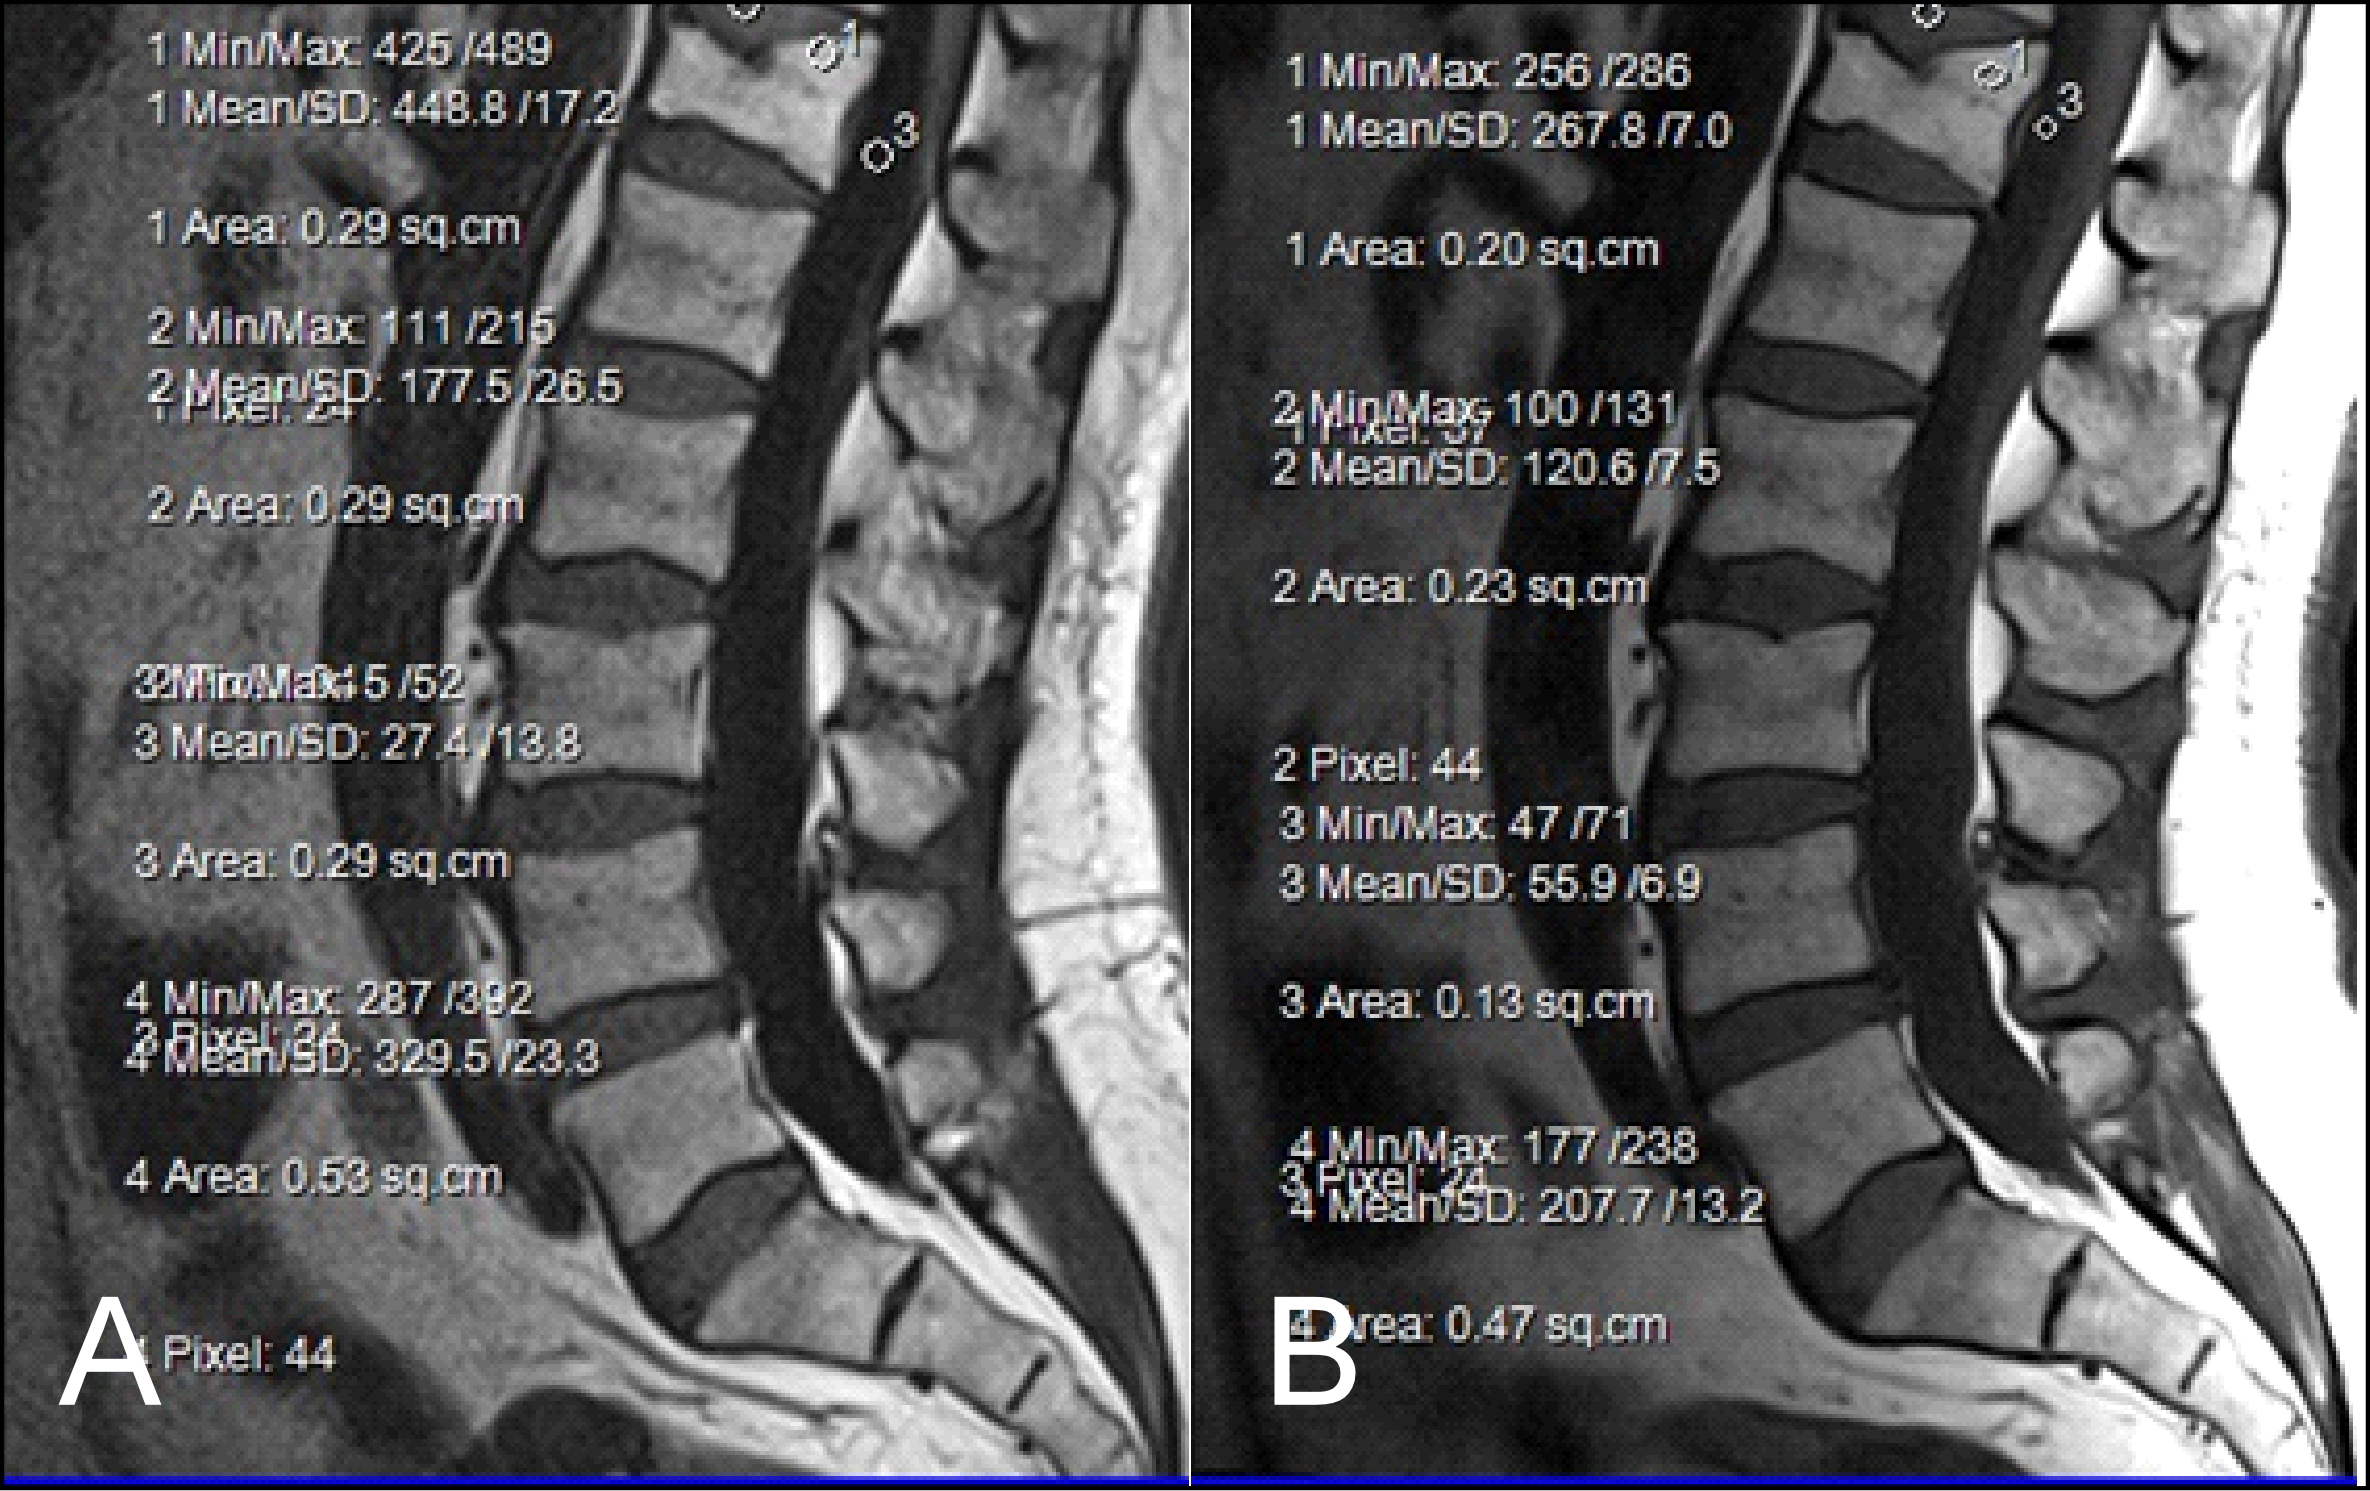

The results obtained from the quantitative analysis of this study showed that the SNR and CNR results were significantly greater for T1W-FLAIR BLADE. More specifically, T1W-FLAIR BLADE sequence achieved better CSF nulling and better contrast between spongy bone and intervertebral disc as well as between spongy bone and intervertebral disc with CSF (Figure 2). A study by Alibek et al., has also demonstrated the superiority in image contrast of T1W-FLAIR images showing that they achieve better lesion to background and grey to white matter CNR [19]. The inherent restrictions of parallel imaging, i.e., reduction of SNR and increased possibility for reconstruction artifacts, were confirmed in our findings where the images without parallel imaging had better SNR (Figure 3).

As stated earlier, sagittal T1 weighted images play an integral role in the MR imaging of the L-spine. One of the reasons is that they provide great information about anatomical structures. In order to assess the importance of the BLADE sequence compared to a TSE, both a qualitative and quantitative analysis were performed by evaluating contrast in between anatomical structures and the SNR, CNR and ReCon measurement respectively [18]. Although T1W-TSE is a faster sequence, T1W-FLAIR BLADE scored better in quantitative and qualitative analyses. Pathologies and abnormalities were better visualized in the latter one. Furthermore, in T1W-FLAIR BLADE there was improved image contrast as well as greater depiction of anatomical structures and either degeneration or metastatic lesions. Both the quantitative and qualitative analysis showed that T1W-FLAIR BLADE achieved better results than T1W-TSE. In addition to that, T1W-FLAIR BLADE images without parallel imaging were found to have better quality than the T1W-FLAIR BLADE images with parallel imaging. Although they both eliminated motion artifacts, the images without parallel imaging have better SNR as well as better contrast between tissues (Figure 3). Moreover, a study showed that T1W-FLAIR images can successfully eliminate chemical shift artifacts compared to T1W-TSE due to greater receiver bandwidth [8]. This statement was confirmed by our findings (Figure 4).